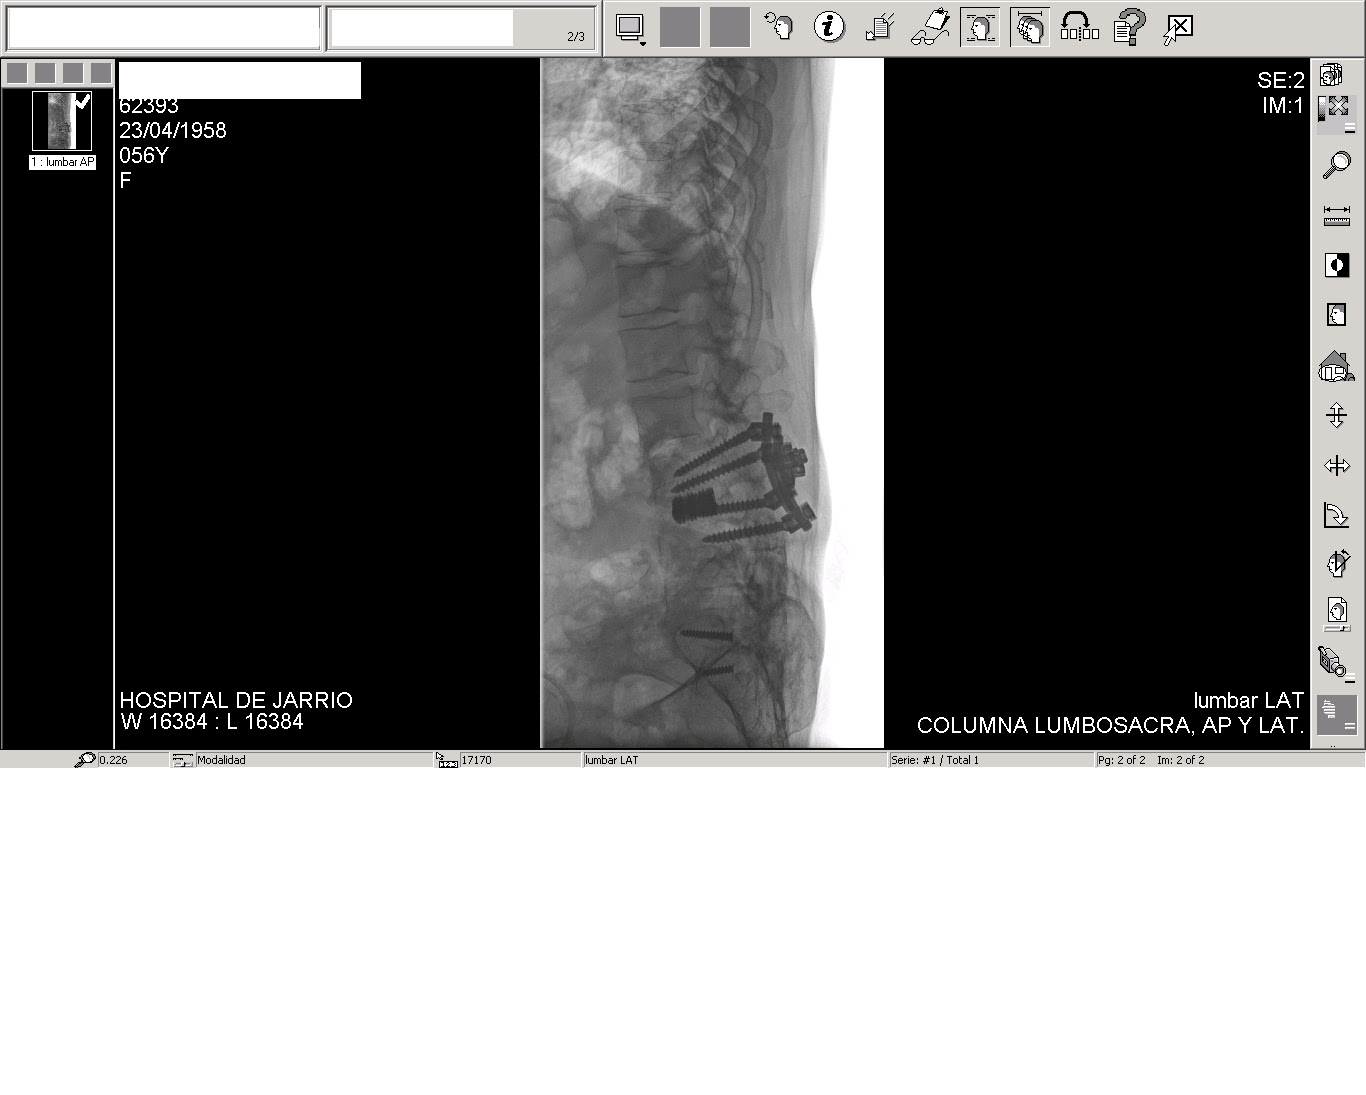

Fotografias de la cirugia: Artrodesis lumbar posterolateral instrumentada

Source: www.cirugiaarticular.com